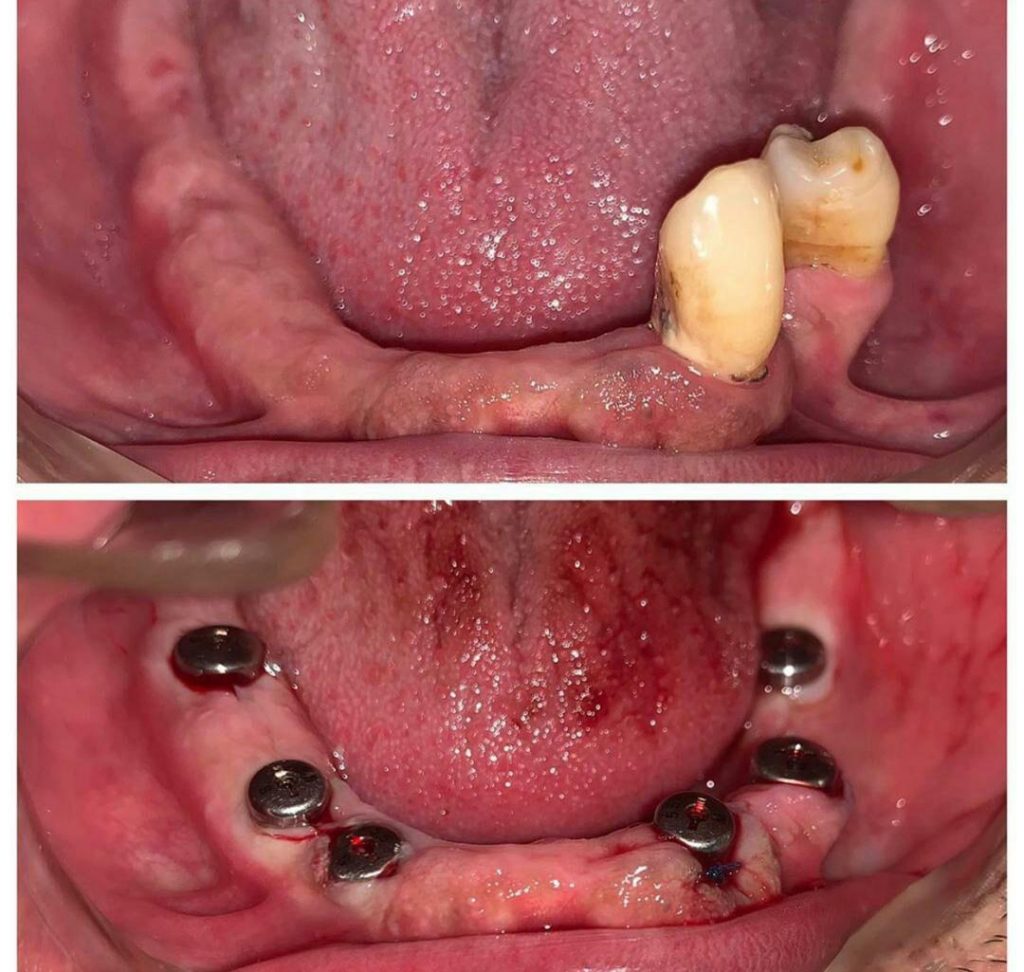

جراح دندانپزشك

متخصص بيماريهاي دهان، فك و صورت

فلوشيپ ايمپلنت از ICOI آمريكا